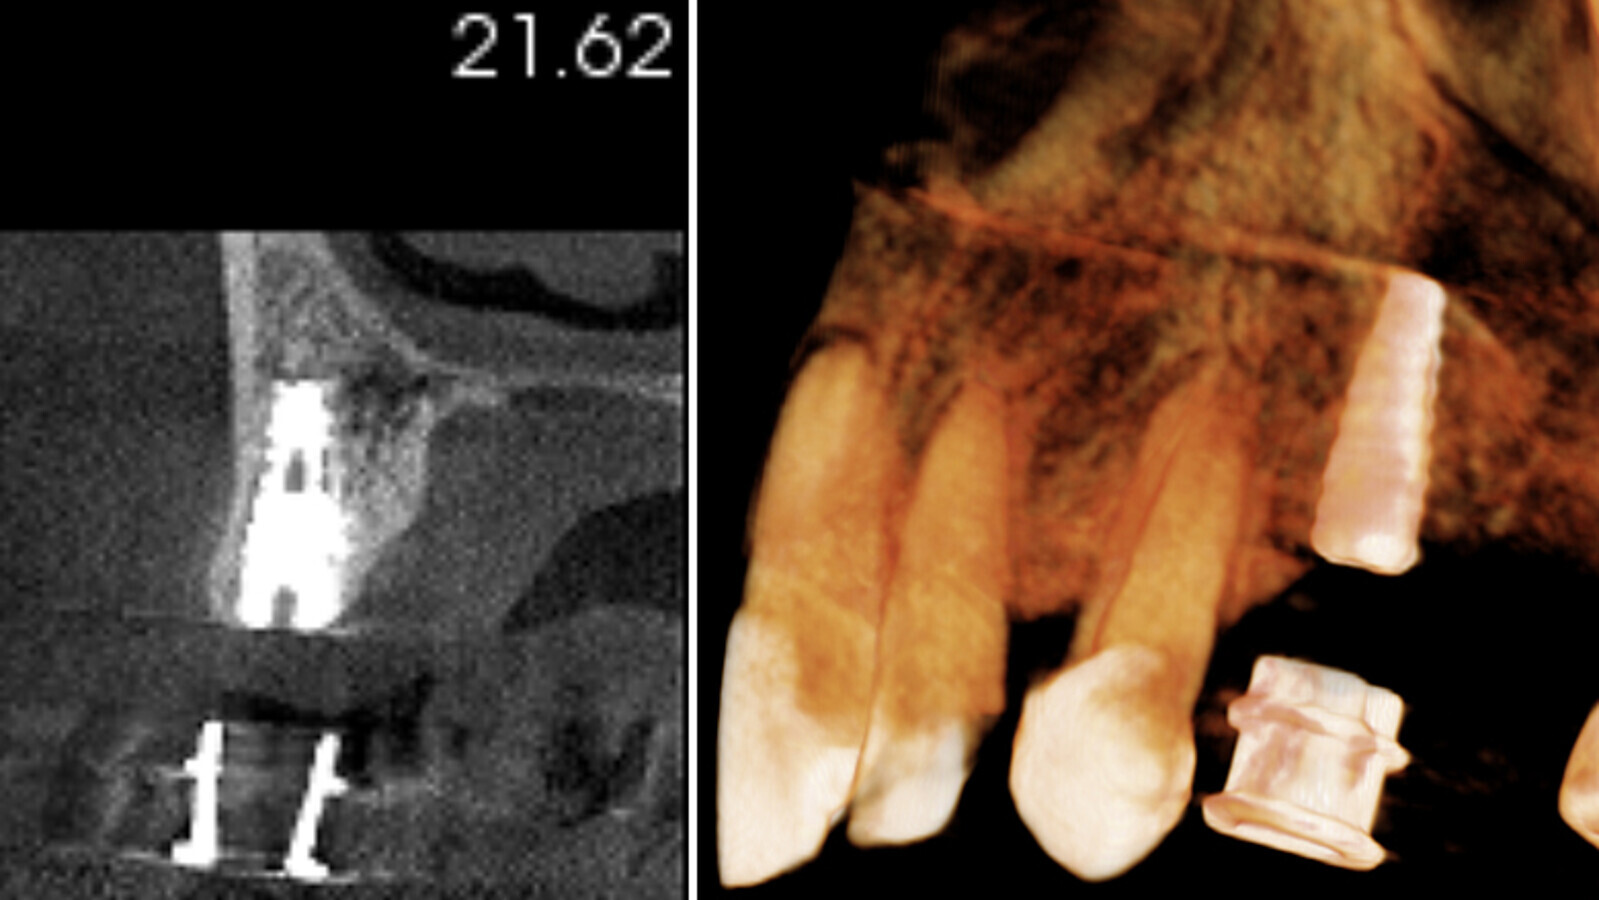

Figuras 6a, 6b. Tomografía Cone Beam post-quirúrgica.

Figuras 7a, 7b PRE Qx. En la tomografía Cone Beam pre-quirúrgica se observa la planificación digital del implante en cuanto a su angulación, dirección y posicionamiento.

Figuras 7a, 7b POST Qx. En la tomografía post-quirúrgica se evidencia el implante ya colocado en boca de igual forma a cómo se realizó en la planificación inicial, lo que confirma que esta técnica muy efectiva para el especialista, y que además minimiza riesgos.